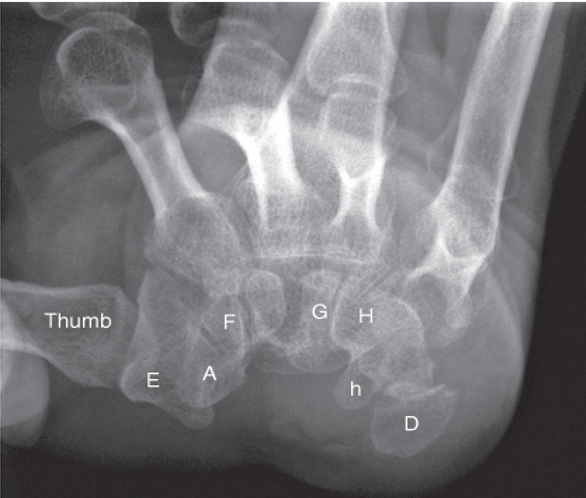

What projection is this?

A

AP Axial foot

(CR at base of 3rd MCT, 10-15º cephalic depending on arch of foot)